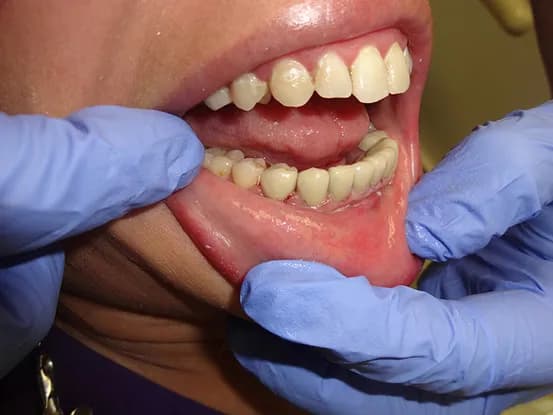

Case 7

38 year old female with extensive cervical caries from a high sugar diet and poor oral hygiene. 12 units of porcelain crowns and composite fillings to restore form and function followed by frequent recall visits